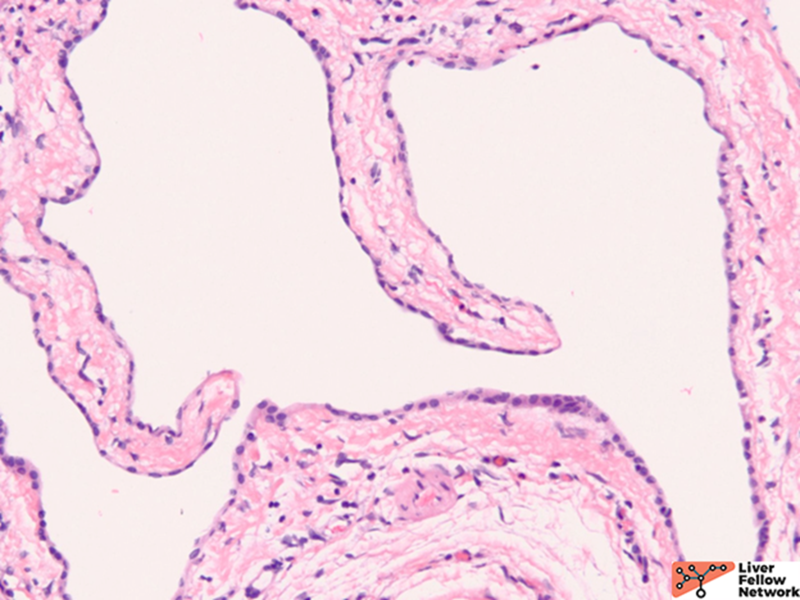

Figure 3. Medium power magnification shows the cystic lining composed of flat and bland cuboidal epithelium. Small bile ductular proliferation can be seen (Arrow).

Histologically, there are cystic spaces of various sizes occasionally accompanied with Von Meyenberg complexes, which showmis-shaped dilated bile ducts lined by cuboidal cells in a fibrotic stroma.

The lining of the cysts consists of simple cuboidal biliary cells in a thin wall of fibrous tissue. Residual hepatocytes may be present beneath the fibrous layer.7